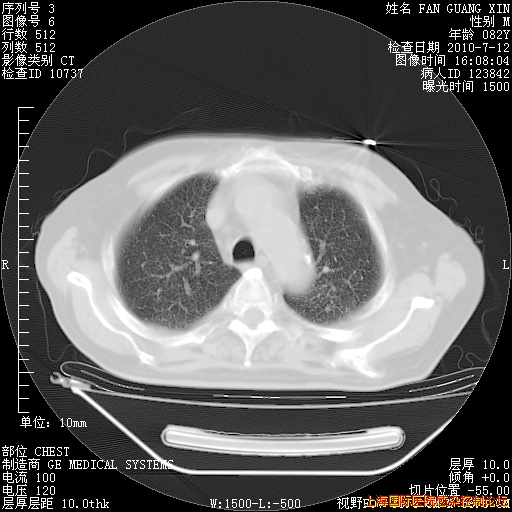

补发6月12日肺部CT肺窗

6月12日肺窗

6月12日纵膈窗

整整相隔30天的肺部CT好像有所好转啊。甲强龙减量第3天,需要观察体温。

海管,自昨日你和我通完话后,不知您岳父消化道症状有无缓解?体温怎样?阅读7.12日胸部ct,个人认为目前激素治疗是有效的,甲强龙减量是适宜的。因在抗痨治疗,需密切观察肝功、肾功能和血常规。不过,老年、长期住院和大量使用激素,很担心菌群失调发生